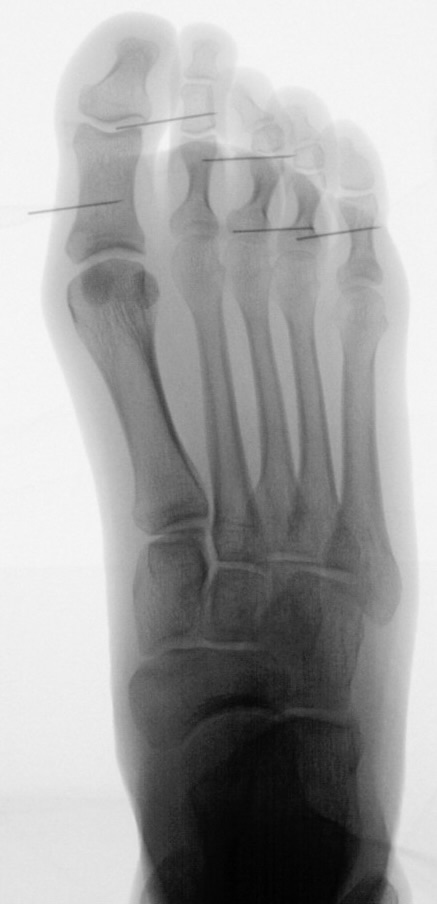

Abb. 2 a-c: offene Wachstumsfugen MT I Basis und Zehen (a), teilweise geöffnete Wachstumsfugen (b) und geschlossene Wachstumsfugen (c).

In der Regel bestehen aktive Wachstumsfugen bei Mädchen bis zum 12. und bei Jungen bis zum 14. Lebensjahr, mit Abweichungen von einem Jahr nach unten und nach oben. Präzise Informationen unter anderem darüber gibt das präoperative Röntgenbild (Abb. 2).